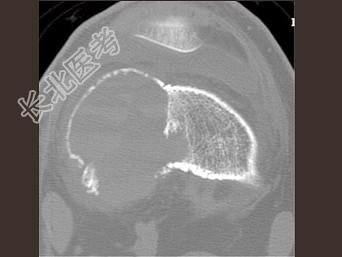

- 单项选择题男,24岁, 左大腿及膝部痛,结合图像, 最可能的诊断是 ( )

A、骨巨细胞瘤

B、骨囊肿

C、成软骨细胞瘤

D、动脉瘤样骨囊肿

E、骨肉瘤